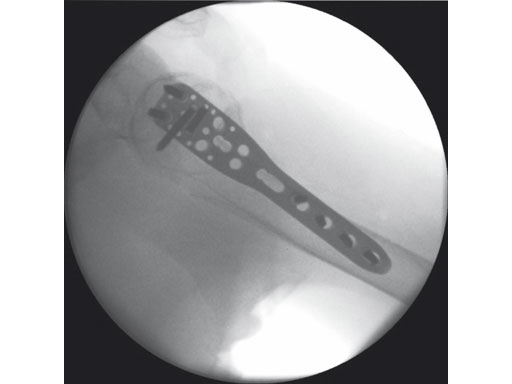

A 76-year-old woman suffered a low-energy fall at home.

Fig 5 Intraoperative view of final result.